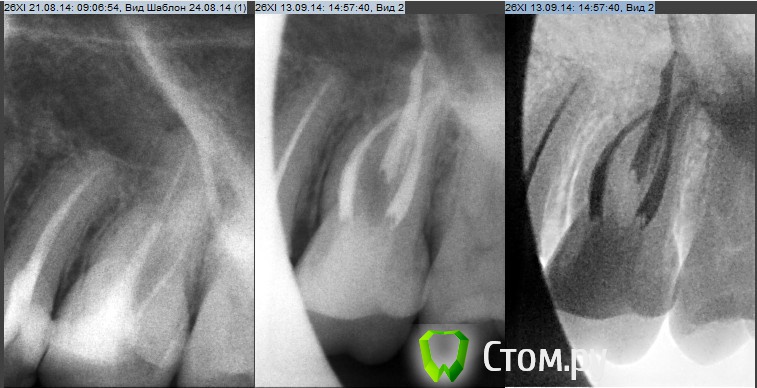

Рустам Опубликовано 20 сентября, 2014 Автор Поделиться Опубликовано 20 сентября, 2014 Проводил повторное эндолечение 26 зуба. Каналы перелечили, стенки достаточной толщины, феррул есть везде, решил восстановить пломбой, следующий этап иск. коронка. на снимке увидел пору в устье небного канала, устья заливал жидкотекучим эстелайтом. Как считаете надо снимать пломбу и закрывать пору? У кого какие мнения на этот счет? Ссылка на комментарий

Рустам Опубликовано 20 сентября, 2014 Автор Поделиться Опубликовано 20 сентября, 2014 Вы говорите про устье? Где, где а в устье такой поры быть не должно, там же все видно. Почти треть канала не закрыта. Думаю все же текучий неконтрастный. Есть снимок после пломбировки канала без постоянной пломбы?Да, речь идет про устьевую треть небного канала. Обычно ставлю канюлю от шприца жидкотекучего композита прямо на гуттаперчу и выдавливаю по одному миллиметру, здесь же торопился очень, смена заканчивалась и сам даже не помню как и что делал. Может и не проконтролировал. Больше всего склоняюсь что это пора, есть снимки с этим же материалом в устьевой части там такая же контрастность, что и у традиционного композита. Если это пора, есть очень веские основания для снятия пломбы в данном случае, как считаете?PS снимка без пломбы нет. Ссылка на комментарий